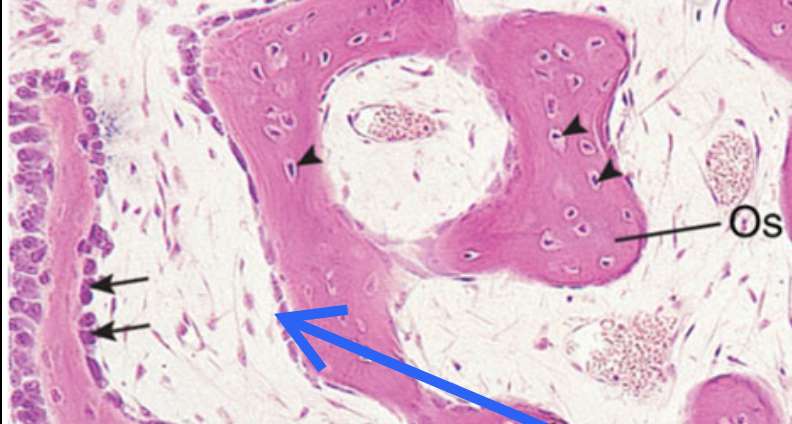

Endoste

recouvre surface interne de l’os

tapisse l’os compact adjacent à la cavité médullaire (endoste cortical), les travées osseuses d’os spongieux qui bordent la moelle osseuse (endoste trabéculaire) ainsi que les canaux de Havers (endoste ostéonien)

se compose de cellules ostéoprogénitrices → peuvent se différencier en ostéoblastes

cellules ostéoprogénitrices et les cellules bordantes

de forme aplatie, ac des noyaux allongés